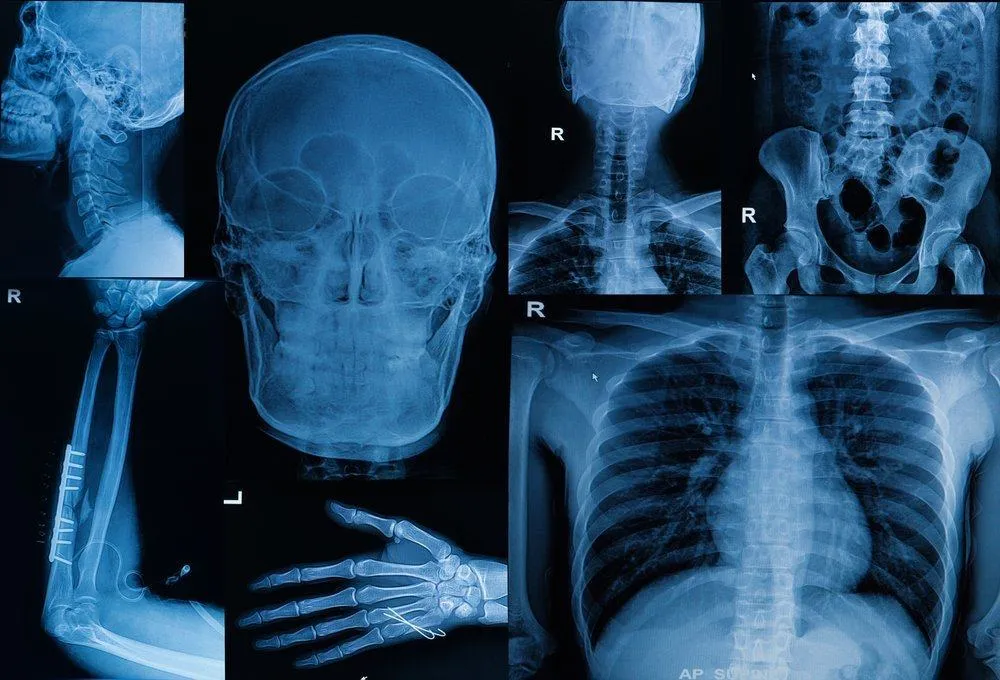

Pada saat mendiagnosis, dokter akan menanyai riwayat medis Anda dan keluarga Anda. Kemudian, untuk menentukan letak, ukuran, serta jenis tumor, dokter akan melakukan tes-tes tambahan. Umumnya, tes yang dilakukan adalah: